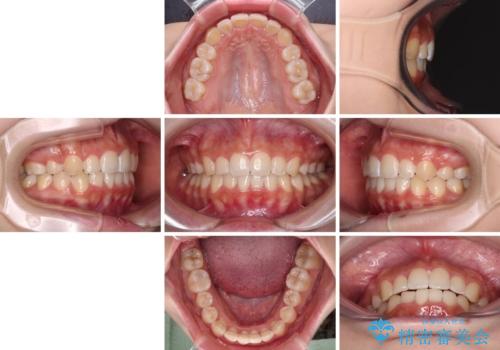

前歯部のデコボコがなくなったため、歯磨きしやすくなり、非常に清潔な状態になりました。